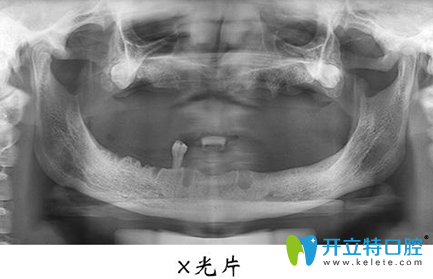

宏沅膛口腔面診的醫(yī)生非常細(xì)心也很有耐心,我不懂的牙齒問題都會很有耐心的告知我,在牙齒種植術(shù)前,需要進(jìn)行常規(guī)的身體檢查,拍攝X光片,了解失牙區(qū)的骨質(zhì)和骨量,以確定是否適宜進(jìn)行牙齒種植等…